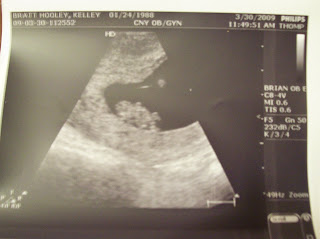

It's Friday already! So, we had our appointment on Monday and everything looked normal! The baby now looks like a baby and not like a dinosaur! S/He has a little body, arms,legs and a head! I think this baby has my dads dancing gene, cause at the ultrasound he or she was dancing all over the place! :) It was so cool! The heartbeat was 189 beats per minute, a lot faster than the 7 week U/S. My doctor wasn't what I had expected based on the reviews I read. He was very short with Chris and I. He cut both of us off mis sentence numerous times. Chris spoke up & I was proud. I'm being transferred to the perinatal specialists due to being high risk. I'm OK with that though. Especially since, a. I don't like this doctor, b. I'll have better care & be watched closer and c. I think it's a little closer!